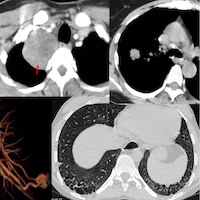

Lecture: Lung Cancer Screening in a TB Endemic Country - A Radiologist's Perspective

It is unlikely that the presence of TB in endemic countries will affect the utility of LDCT for cancer detection in smokers, as long as the radiologists and pulmonologists have good interpretation skills and these patients are managed in a multidisciplinary setting

The main focus of the lecture is the pickup of active latent, asymptomatic lesions in smokers that turn out to be TB lesions that need treatment - are these false positives or are these part of the process of picking up nodules that need treatment, whether cancer or TB?